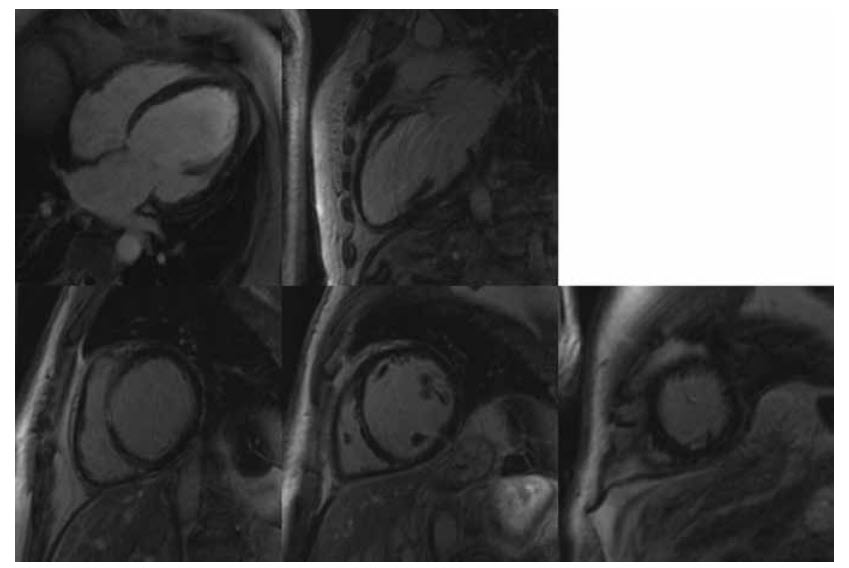

Figure below shows late myocardial enhancement following gadolinium in the four- and two-chamber views (top row) and at the basal, mid, and apical levels (bottom row, left to right).

Dilated cardiomyopathy (DCM). There are increased LV volumes with global, not regional, LV systolic dysfunction. There is a thin band on mid-wall myocardial late enhancement in the septum in keeping with DCM.